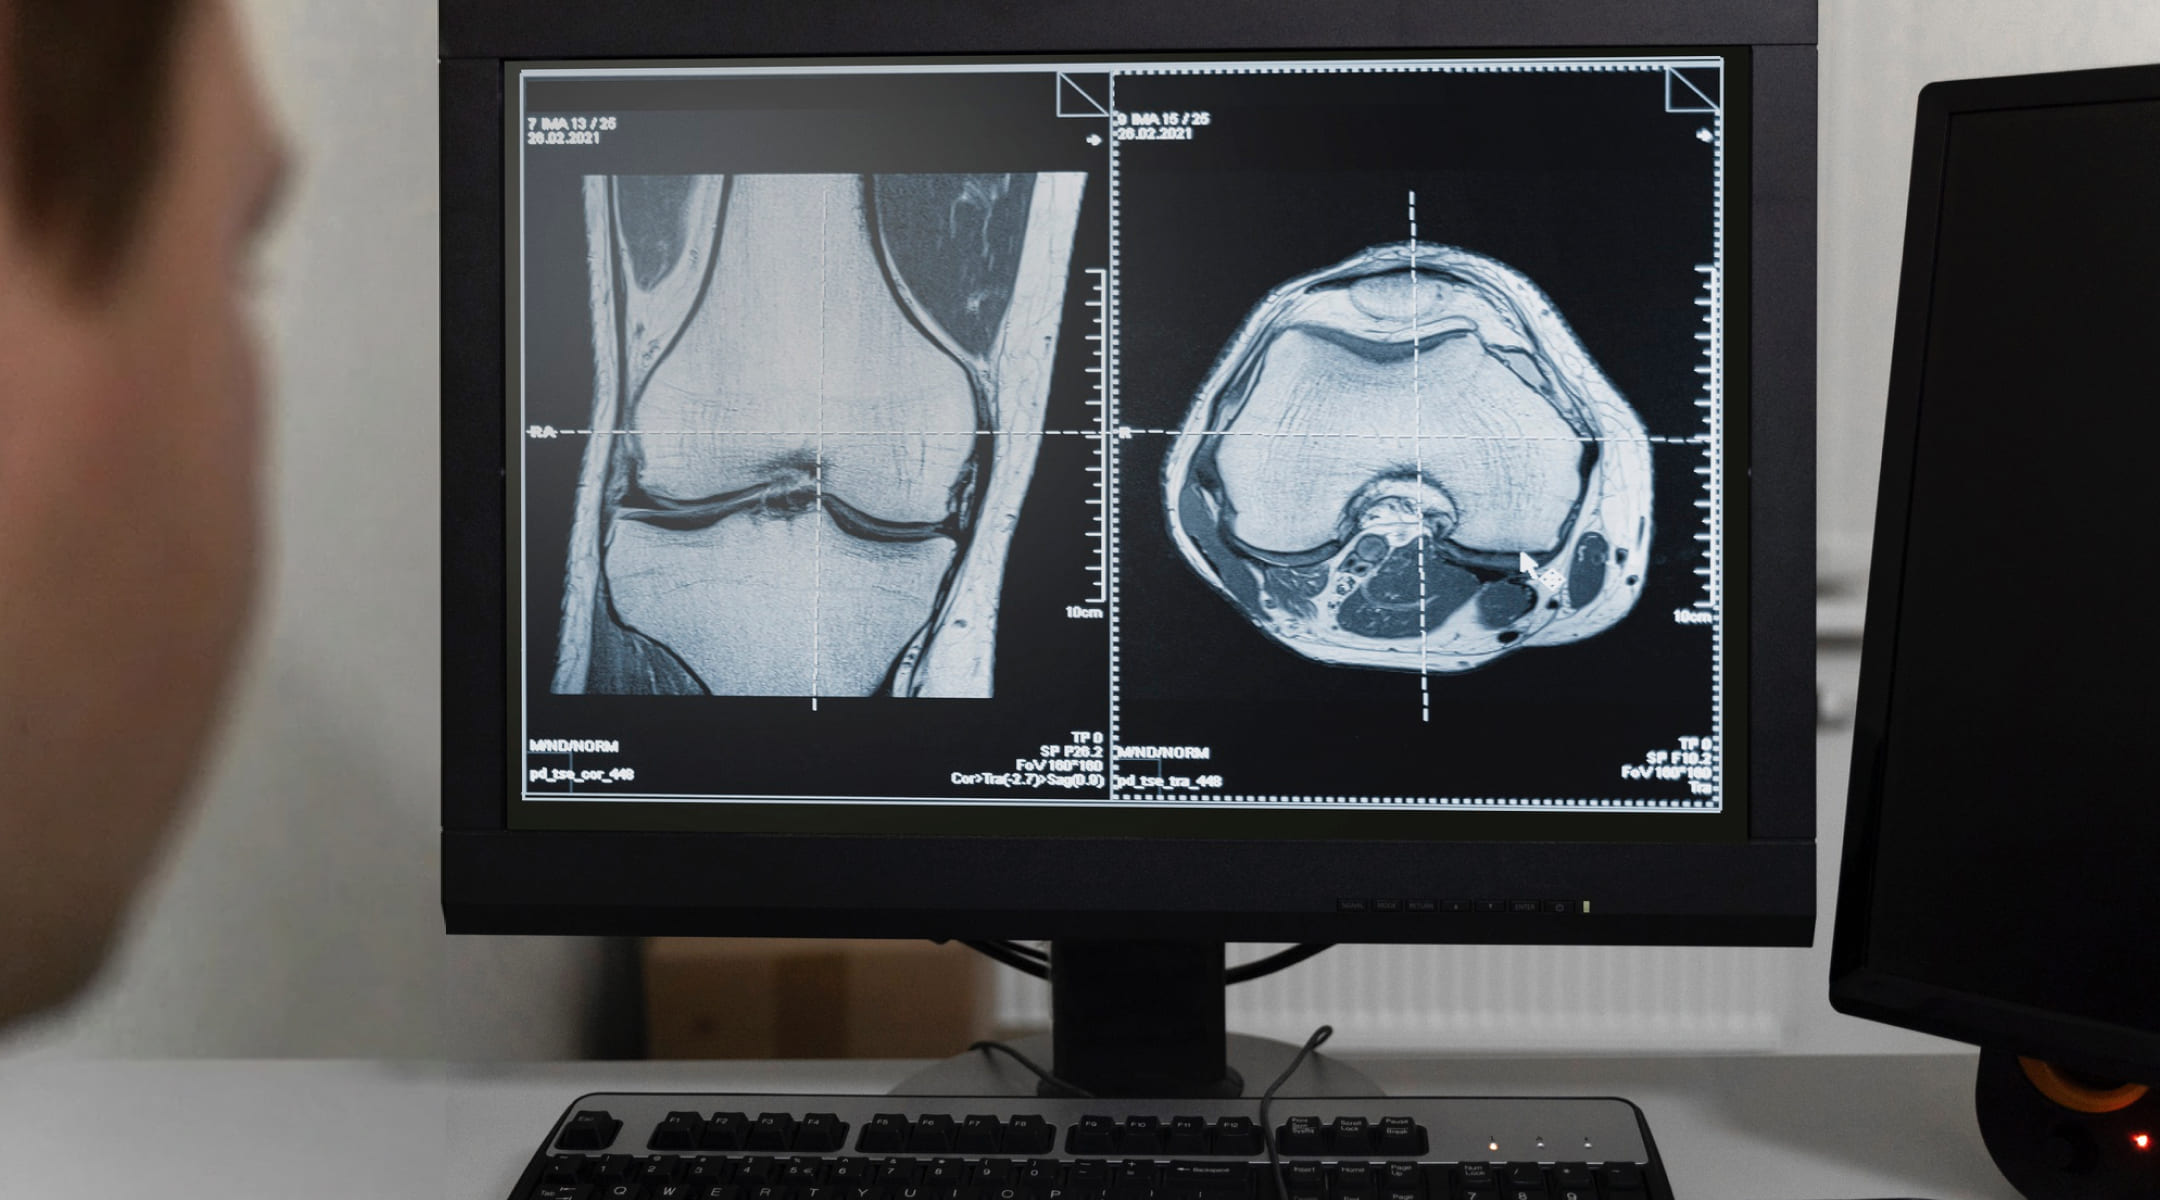

- Конкретные диагнозы, подтвержденные МРТ. Полный разрыв передней крестообразной связки у активных пациентов (требует пластики ПКС), крупные нестабильные разрывы мениска, очаговые повреждения хряща 3-4 степени (требующие восстановления хряща колена), наличие свободных внутрисуставных тел.

Подготовка начинается с комплексной диагностики: осмотр ортопеда-травматолога, МРТ коленного сустава (наиболее информативный метод), рентген, стандартные анализы крови и мочи, консультация терапевта и анестезиолога. Врач подберет тип анестезии – чаще всего это спинальная анестезия или общий наркоз. Важно обсудить с хирургом все детали: от принимаемых лекарств (особенно разжижающих кровь) до послеоперационного ухода. За несколько дней до малоинвазивной операции на колене рекомендуется отказаться от курения и алкоголя для улучшения процессов заживления.